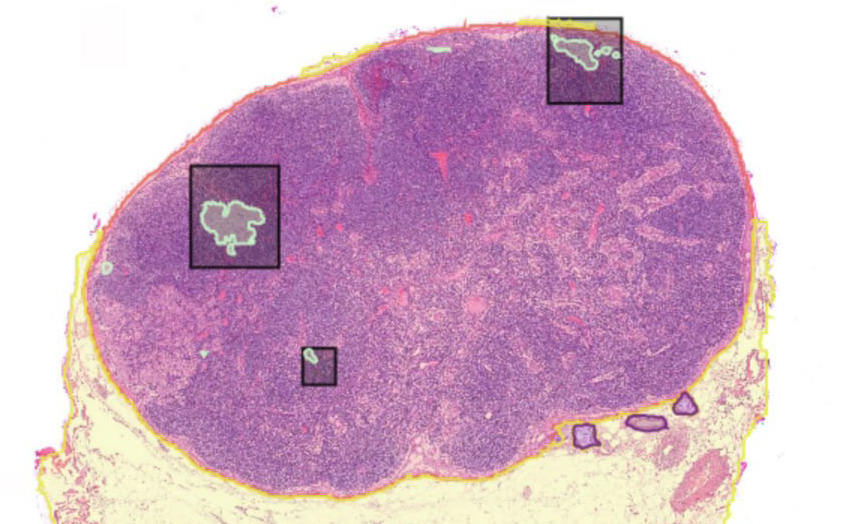

AI-assisted lymph node screening and metastasis detection in whole slide images, enabling automated N-staging for multi-cancer pathology workflows.